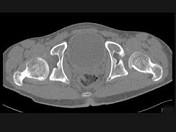

问题 男,23岁,跛行,外展受限,两下肢不等长,结合图像,最可能的诊断是?(?)

选项 A.髋关节中心脱位 B.髋关节后脱位 C.髋关节前脱位 D.先天性髋内翻 E.髋关节结核

答案 B